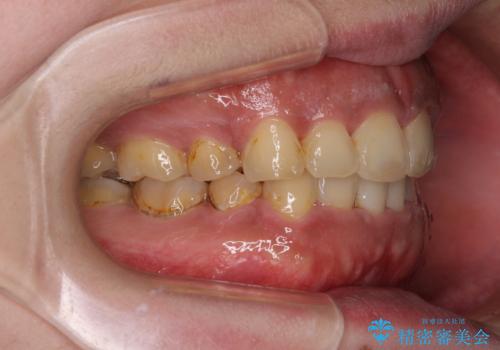

- 口元の突出感と上下前歯のでこぼこを気にして来院された患者様です。

上下前歯部叢生のスペース獲得のため、上下顎左右小臼歯各1歯(計4本)を抜歯して、矯正治療を行うこととしました。

口腔内の清掃性に問題があり、虫歯のリスクが極めて高かったため、短期で治療を終えることを最優先に治療を進めました。